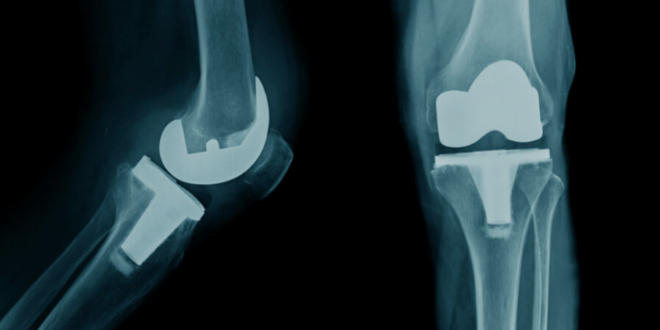

Surgical treatment for damaged knee joints with artificial ones that are designed to imitate the functions of a knee joint, arthroplasty, or more commonly knee replacement surgery, is aimed at reducing pain and improving mobility to restore natural movement. Thanks to modern practices, such as cutting edge surgery, recovery time has decreased and discomfort is less with long-term successful results.